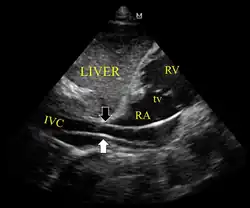

Ultrassonografia mostrando o dispositivo no ventrículo direito -

Dispositivo passando de forma inadequada para a veia cava inferior -